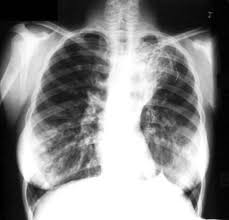

Tantangan di Balik Keberhasilan Program TB

Jakarta (Jaringnews.com) – Indonesia mendapatkan Achievement Award dari Global Health USAID sebagai negara yang paling berhasil dalam mengatasi permasalahan Tuberkulosis (TB), Rabu, (20/3) lalu.